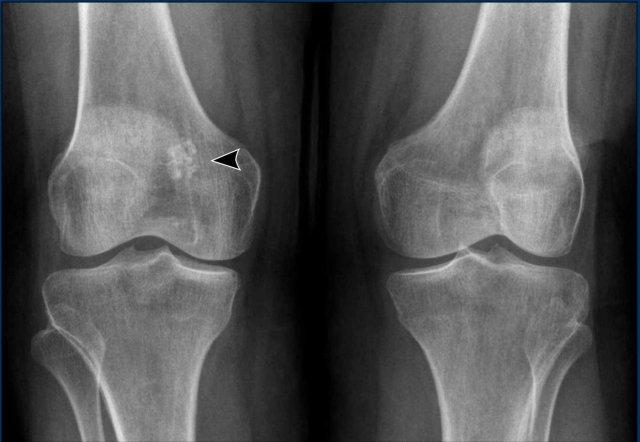

Enchondroma (U Sụn Nội Xương)

U sụn lành tính (Enchondroma) được coi là “mô sụn lạc chỗ”.

Do đó có mối liên hệ chặt chẽ với sụn tăng trưởng đầu xương, thường trong phạm vi 2 cm.

U sụn lành tính thường được tìm thấy ở hành xương đầu trên xương cánh tay, đầu dưới xương đùi hoặc đầu trên xương chày.

Các tổn thương lành tính này xuất hiện như những phát hiện tình cờ trong 3% tổng số MRI khớp gối và không cần theo dõi thêm.

U sụn lành tính có thể phát triển chậm theo thời gian hoặc thậm chí tự thoái triển.

Bản thân sự tăng trưởng không phải là dấu hiệu cho thấy tổn thương đã trở thành ác tính.

Enchondroma thường nhỏ hơn 5 cm và 80% enchondroma ở xương dài nhỏ hơn 2 cm.

Các ngưỡng kích thước khác nhau được đề xuất để phân biệt enchondroma với ACT và sarcoma sụn.

Trong tiêu chí BACTIP, ngưỡng 4 cm được sử dụng để quyết định liệu một tổn thương có cần được theo dõi hay không.

Tại cơ sở chúng tôi, chúng tôi sử dụng 5

cm làm ngưỡng giới hạn, tuy nhiên cần lưu ý rằng không có giá trị ngưỡng kích thước tuyệt đối

và bạn luôn phải loại trừ các đặc điểm xâm lấn, vì có thể có

các u sụn ác tính độ cao nhỏ hơn 5 cm phát triển xuyên qua vỏ xương và

kèm theo khối mô mềm.

U sụn trong điển hình

Các hình ảnh cho thấy hai tổn thương nhỏ liền kề với đĩa tăng trưởng ở vùng hành xương đầu xa xương đùi, đại diện cho các phần sụn nhỏ không liên quan đến vỏ xương hoặc phù tủy xương quanh tổn thương.

Không cần theo dõi thêm.